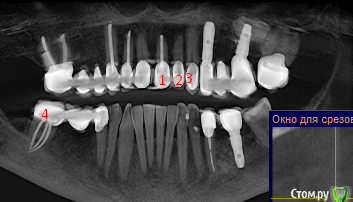

ellenchik Опубликовано 3 мая, 2018 Автор Поделиться Опубликовано 3 мая, 2018 Уважаемые Доктора! Я снова к Вам с просьбой. Продолжу мою тему.После депульпирования 21 зуба, боль в области трех обозначенных на снимке верхних передних зубов осталась прежней. Появляется спонтанно в любое время. На перкуссию - спокойно. Боль жгучая,ноющая,разлитая.Иногда отдает в переносицу. Врач говорит,возможно у зуба № 2 большая пломба давит на нерв. Я ощущаю часто боль в зубе № 3. Несколько дней может быть всё спокойно. Принимаю Ибупрофен 400. Иногда помогает иногда нет. Ощущение,что болят эти 3 зуба. Конкретно уже не могу сказать. Будучи проездом в Питере ,сделала 3 Д томографию,но только диск без описания, к врачу не попала, к сожалению. Здесь врач (в Германии в маленьком городке ) с этим не работает. Посмотрите ,пожалуйста, общий срез-снимок. Зубы 1-2-3. Номер 1 депульпирован в январе, как предполагаемый источник проблемы и боли. Подскажите,пожалуйста, какие срезы сделать и выложить для бОльшей информативности. Очень надеюсь на Вашу помощь. Спасибо всем откликнувшимся. С уважением Елена Ссылка на комментарий

kramer Опубликовано 4 мая, 2018 Поделиться Опубликовано 4 мая, 2018 Дайте срез через зуб, который вы пометили №3 Ссылка на комментарий

ellenchik Опубликовано 5 мая, 2018 Автор Поделиться Опубликовано 5 мая, 2018 kramer, спасибо за ответ.Срез сделала,но не уверена, что правильно. Подскажите,пожалуйста, если что не так. Буду делать другие. Ссылка на комментарий

ellenchik Опубликовано 7 мая, 2018 Автор Поделиться Опубликовано 7 мая, 2018 ...похоже, я неправильно делаю срезы :-( Подскажите, пожалуйста. Тема по прежнему актуальна. Мой врач предположил, что есть воспаление у зуба № 1 (отмечен на снимке) и предлагает глубокую хирургическую чистку (вероятно резекцию корня) Хотелось бы услышать еще мнения уважаемых докторов. Ссылка на комментарий